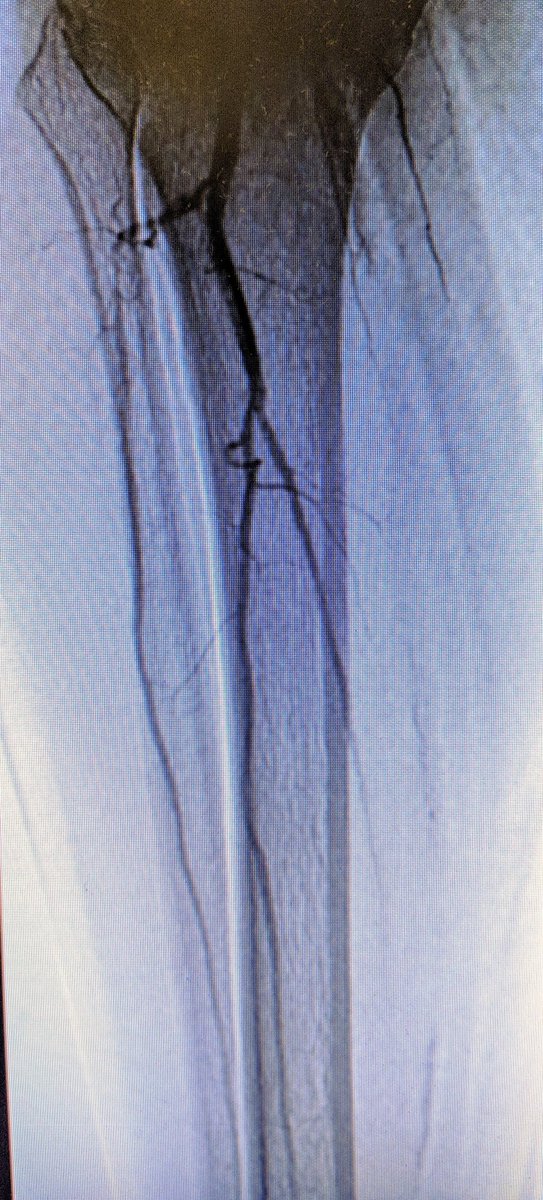

90 y/o F with rest pain, poor op candidate. #CLI #dojustenough #commandwire @abbottvascular @AbbottGlobal #CSI #DCB @BardPV #vesselprepcrucial #nometalleftbehind #stopthechop #CLIfighters #clifighters @DrBTKatzen @SriniTummala @Mustapja @FadiSaab17 @Heartpower717 @drsavealimb